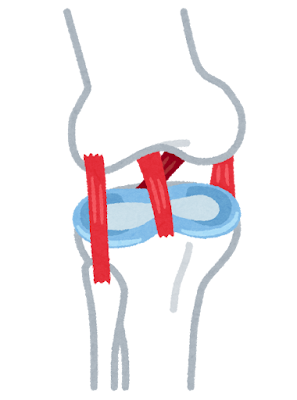

🦵 主な原因

・軟骨のすり減り

・炎症

🔬 医学的にみた原因(重要)

🦴① 軟骨の摩耗(変形性膝関節症)

加齢により関節軟骨がすり減り、骨同士が直接こすれる状態になることで炎症と痛みが発生。特に膝関節は体重負荷が大きく、最も影響を受けやすい部位とされる。

💪② 筋力低下(大腿四頭筋の衰え)

太ももの筋肉が弱ることで膝関節を支えられなくなり、関節への負担が増大。結果として関節の変形や炎症が進行し、慢性的な痛みへとつながる。

🔥⑤ 炎症の慢性化

関節内の炎症が続くことで痛み物質が増加し、痛みが長期化。炎症を放置すると関節の変形が進行し、日常生活に支障をきたす。